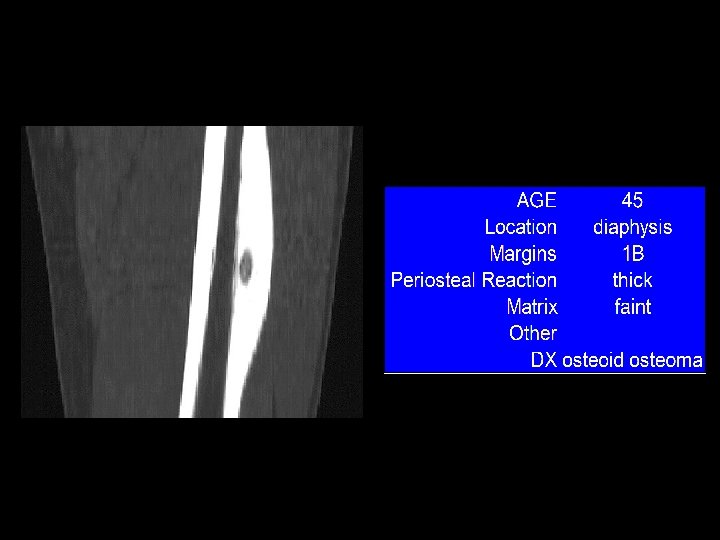

Example 8: 45 y/o with thigh pain

Example 8